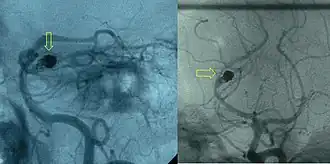

Access to the organ in question is acquired by means of a guidewire and catheter(s). Depending on the organ this can be very difficult and time-consuming. The position of the correct artery or vein supplying the pathology in question is located by digital subtraction angiography (DSA). These images are then used as a map for the radiologist to gain access to the correct vessel by selecting an appropriate catheter and or wire, depending on the 'shape' of the surrounding anatomy.

Once the artificial emboli have been successfully introduced, another set of DSA images are taken to confirm a successful deployment.